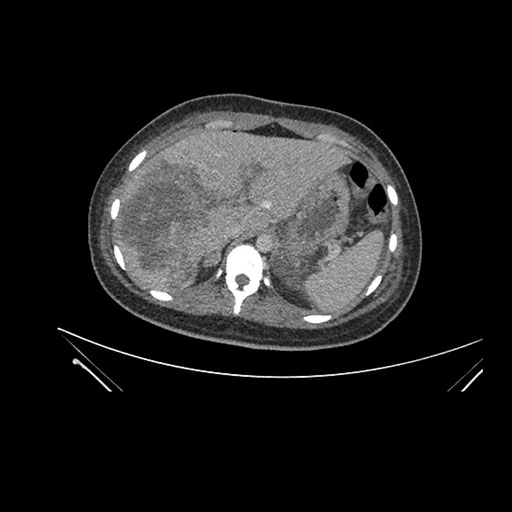

Axial Venous